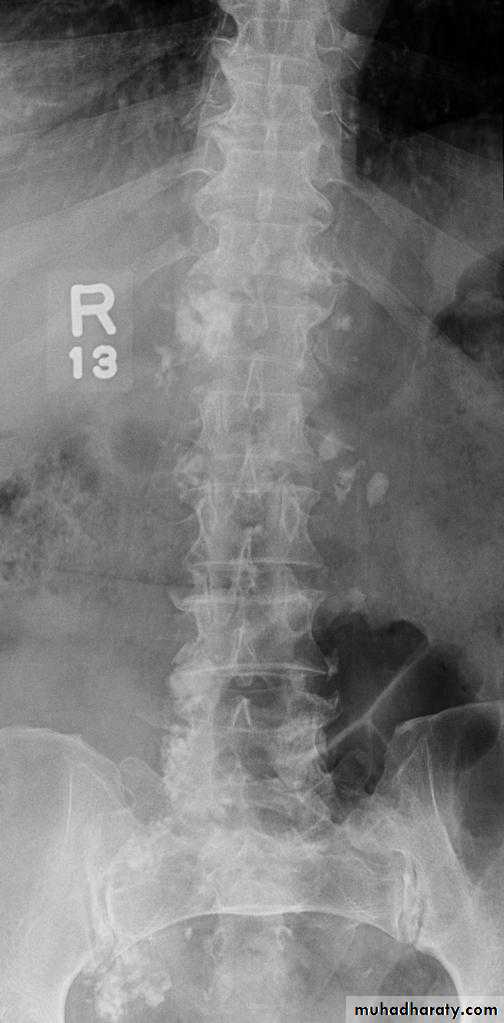

Abdominal calcifications

3. Vascular calcification: e.g. aortic aneurysm which best assessed on lateral film

11. Pancreatic calcification: occur in chronic pancreatitis & diagnosed from it's position